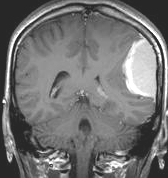

典型的な髄膜腫

この髄膜腫は中程度の大きさのものです。円蓋部髄膜種という最も多い最も手術の簡単なタイプです。麻痺や失語症やてんかんなどの症状はありません。とても美しくて若い女性の髄膜腫でしたが,子供に遺伝はしませんし,癌などと違ってタバコなどこれといった原因がなくて発生するものです。

MRIでの髄膜腫の見え方は撮影の仕方によっていろいろです。左からT1強調画像,T2強調画像,フレア画像といいます。腫瘍の横に小さく白い領域がありますが,これは脳の腫れた部分で脳浮腫といいます。髄膜腫があると周囲に脳浮腫が生じることがあります。

最も見やすいのが,ガドリニウム造影剤を注射して撮影するものです。一般的に髄膜腫は造影剤で白く映し出されます。この腫瘍は左脳側にあります。MRIの軸面という輪切りの写真では左右が逆になりますから注意してください。脳を下から見た図になっています。MRIはいろいろな方向から腫瘍を見ることができますが,右は冠状断という正面から見た図です。よく見ると腫瘍の上と下のはじっこに線状に糸を引いたように造影される部分があります。これをテールサイン(しっぽのサイン)といいます。腫瘍が硬膜に沿って延びている可能性があることを示しています。